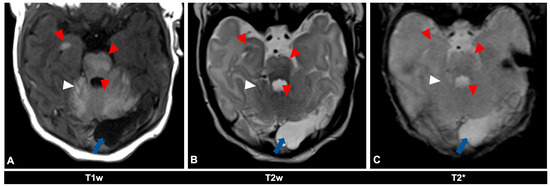

Figure 2.

MR imaging of an 11-day-old female patient with neurocutaneous melanosis (NCM) using an MRI-compatible incubator. (A–C) Imaging findings of leptomeningeal (white arrowhead) and intraparenchymal melanosis (red arrowhead) demonstrate a high T1 signal, especially in the pons, cerebellum, and amygdala. These findings are not sufficiently detectable in T2-weighted (B) or T2 star (C) sequences (white arrowhead), at most a slight signal reduction in T2-weighted sequences. The patient also has an infratentorial arachnoid cyst (blue arrow). Spinal MRI showed no abnormalities (not shown). T1w = T1-weighted; T2w = T2-weighted; T2* = T2 star.